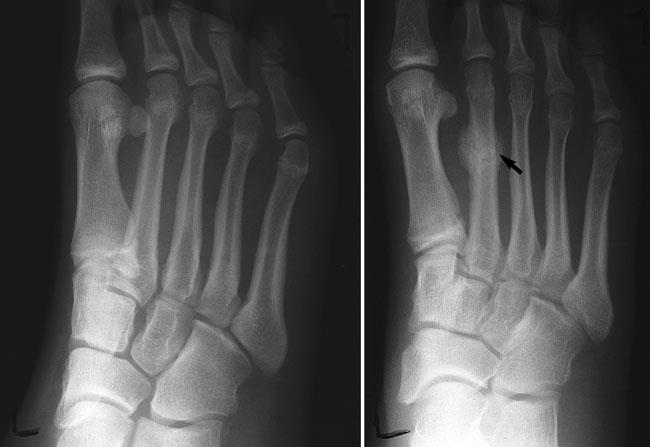

زمانی که به ملاقات پزشک متخصص رفتید، روشهایی برای تشخیص واکنش استرسی روی ناحیه موردنظر انجام میشود. در بعضی موارد، آنها ممکن است براساس معاینه یا تاریخچه پزشکی-ورزشی شما، تشخیص را انجام دهند یا اینکه برای ناحیه حساس به لمس و دردناک، یک تصویربرداری ایکس-ری تجویز کنند تا ببینند آیا نشانههایی از تغییرات استخوانی که نشانگر واکنش استرسی باشد وجود دارد یا نه؛ همچنین از التراساند نیز برای بررسی بهتر استفاده میشود. در مراحل پایانی، اگر پزشک نتواند تشخیص قطعی انجام دهد، ممکن است از امارای استفاده شود.